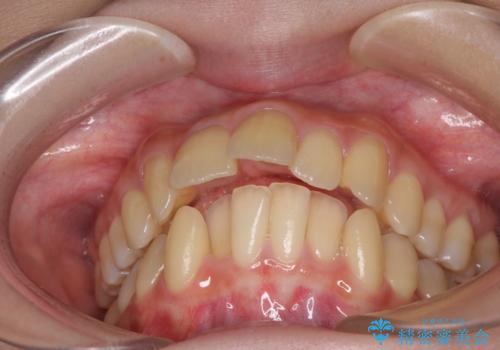

- 上下の出っ歯を気にして来院された患者様です。

口元を積極的に引っ込めるために、上下左右の小臼歯を4本抜歯することとしました。

右上前から2番目の歯が欠損しているため、①矯正治療により欠損部にスペースを作りインプラント補綴を行って前歯を左右対称に揃える、②左右非対称となるが、欠損補綴を行わずに排列する、のいずれかとなりますが、患者様と相談の上②にて矯正治療を行うこととしました。

変則的な歯列であったため、奥歯がしっかりと咬み合うのか、前歯はしっかりと排列できるのかと不安ではありましたが、結果としてはきれいに整った歯列にて終了することができました。